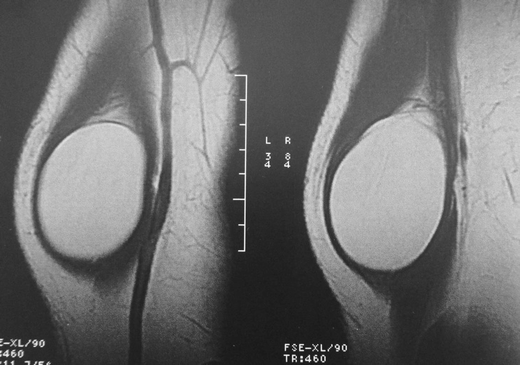

T1 FAT SAT MRI images, showing an intramuscular mass on the supinator muscle

T1 MRI images, showing an intramuscular mass on the supinator muscle